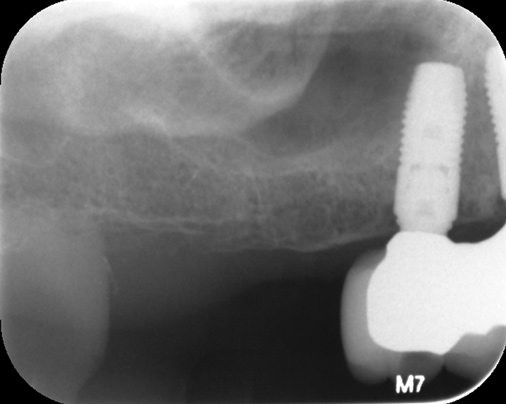

Fig 7. Tilted implant solutions for maxillary posterior partial edentulism. In the same manner that tilted implants can be used to

avoid the need for sinus grafting in full-arch implant prostheses, they can be used to avoid direct or indirect sinus grafting when insufficient posterior

maxillary bone volume challenges a fixed dental prosthesis implant restoration. Fig 7: Software planning for implant placement is shown with

tilting of the distal implant along the anterior wall of the maxillary sinus where there is insufficient bone in zone 3. Fig 8: Postoperative radiograph

of the implants and abutments reveals the angulation of the implant resolved by the CAD/CAM abutment. Fig 9: Final radiograph of the implant

prosthesis following restorations demonstrates the inclusion of a tooth in the molar position without sinus grafting.

Figure 8